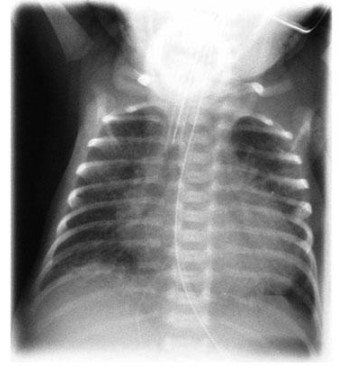

Common X-ray Findings: